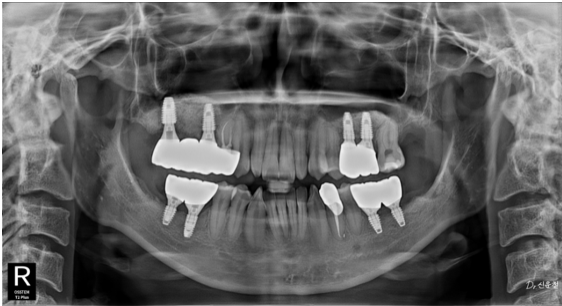

촬영일 : 251117 (임플란트 총 8개 식립 상태)

촬영일 : 260112

결혼식은 하루, 치아는 평생입니다

다솜치과에서는 일정에 맞춰 급하게 마무리하기보다,

현재 상태를 정확히 진단하고

선택 가능한 치료 범위를 설명드린 뒤

일정에 맞춘 계획을 세워드립니다.